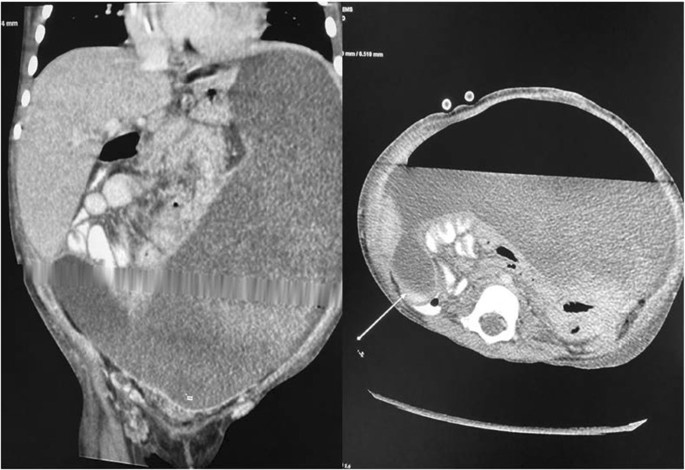

Plain abdominal X-ray revealed abnormal air lucency around the center of the abdomen, suggesting pneumoperitoneum. Abdominal CT findings revealed a huge fluid collection in the abdomen with a large air fluid level, extending from the level of the left hemidiaphragm to the pelvis. Mild enhancement of the peritoneum was noted with peritoneal thickening in the right lower quadrant (Fig. 1). The fluid collection displaced the abdominal viscera superiorly and posteriorly. Mild thickening of the right lateral abdominal wall was noted below the inferior margin of the liver, consistent with EPS. Ultrasound-guided abdominal drain aspirated 500 mL of pus mixed with fecal matter, likely due to bowel perforation. Laparotomy findings included extensive adhesions, fecal fluid, and bowel perforation. The whole bowel was matted together covered by thick membrane; the membrane was densely adherent to the bowel wall, which was difficult to separate (Fig. 2). Therefore, peritoneal biopsy was not done during surgery. An abdominal drain was inserted. A stoma was required but was difficult to create because of matted bowel. Two months later, a stoma was created but complicated by fistula with huge secretion that improved with conservative treatment (Figs. 3, 4). During hospitalization, the patient required a prolonged course of total parenteral nutrition (TPN) for 6 months until the gut healed and due to several instances of sepsis (Fig. 5). The patient made a complete recovery and remained stable on regular HD treatment and gained muscle mass. The child was on hemodialysis for 3 years before getting renal transplant from a cadaveric donor. Two and a half years post renal transplant, she is doing well on triple immunosuppressants (prednisolone, tacrolimus, and mycophenolate malate) without recurrence of EPS.